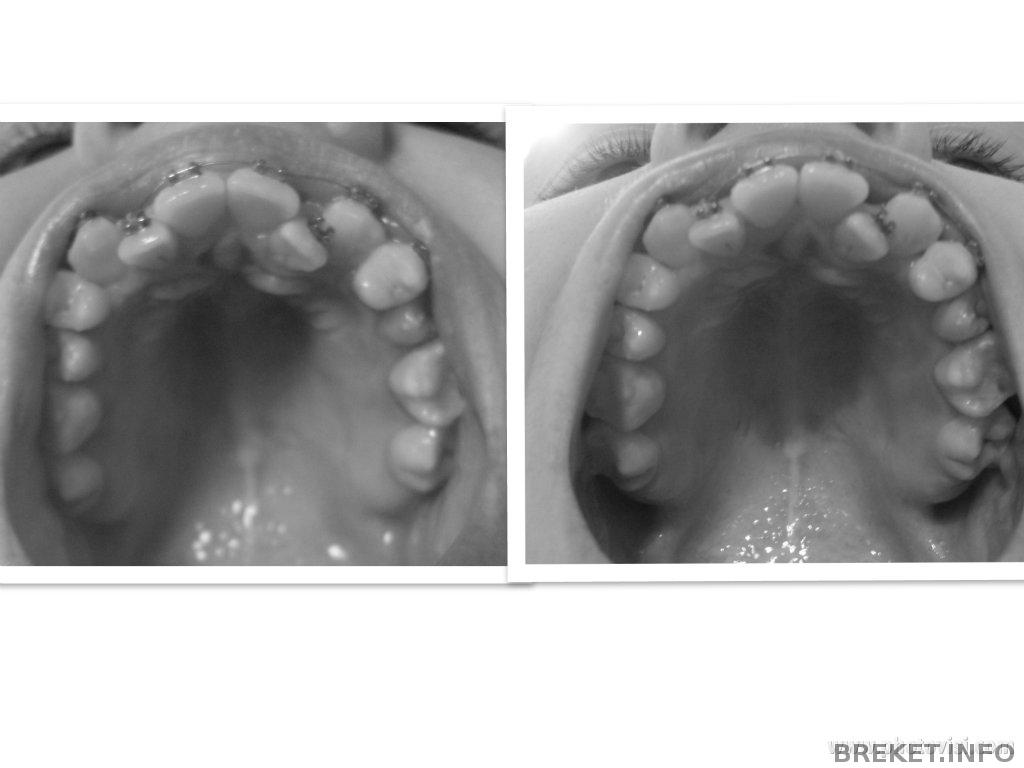

Даже сфоткала,что бы точно понять,что это так,а не мое воображение.

А изменения такие:

-стала щель между единичками

-между двойкой и тройкой правой стала щель

-двойка левая еще на чуть-чуть ушла внутрь((((

-пятерка правая ближе к ряду стала

Собственно смотрите))

неее..это не двойка ушла внутрь....а единичка стала ровнее и отошла от двоечки, поэтому такое впечатление что двойка ушла...потихонечку все встанет на нужные места